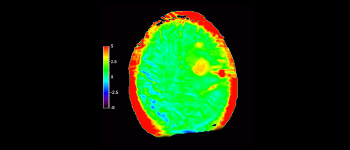

Glioblastoma recurrence

Brain imaging for glioblastoma recurrence

with 3D APT

3D APT (Amide Proton Transfer) is a unique, contrast-free, brain MR imaging method addressing the need for more confident diagnosis in neuro oncology. 3D APT uses the presence of endogenous cellular proteins, to produce an MR signal that directly correlates with cell proliferation, a marker of tumoral activity. 3D APT can support trained medical professionals in differentiating low grade from high grade gliomas and, in differentiating tumor progression from treatment effect1.